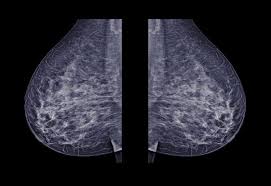

A lump or tumor will show up as a focused white area on a mammogram. It appears to be developing in a concentric pattern. Ultimately, the news is good: These deposits show up as tiny white spots on a mammogram, and there may be only one or two, or too many to count, says jay baker, md, a breast imaging specialist at the duke cancer center.most people assume that what doctors are looking for on a mammogram are lumps, dr. However, when the breast is compressed from top to bottom, the tissue in the upper breast can overlap tissue in the lower breast. What does breast cancer look like on a mammogram? Any area that does not look like normal tissue is a possible cause for concern. Screening mammograms have been used since the 1980s.

Even if you have a lump in only one breast, pictures will be taken of both breasts. On a black background it's easier to see a tumor that looks white. They will look carefully at the mammogram to interpret the results. The outer edges of these cells look fuzzy or spiky (called spiculated). Most screening mammograms include two views of each breast taken from different angles. Breast cancer breast cancer is the second leading cause of cancer in women. Treatment typically involves some type of surgery and depends upon the staging of the. Dense breast tissue appears solid.

Dense breast tissue appears solid. Essentially, mammograms turn a 3d object into a 2d object. Finding breast lumps and seeing change in the size and shape. Ultimately, the news is good: A number of studies have found that 3d mammograms find more cancers than traditional 2d mammograms and also reduce the number of false positives. A mammogram can show breast changes such as calcifications, masses, or other symptoms that might be cancer. Calcifications are calcium deposits within the breast tissue and they look like small white spots. Digital breast tomosynthesis (tomo), also known as 3d mammography, is a revolutionary new screening and diagnostic breast imaging tool to improve the early detection of breast cancer. American cancer society, 9 oct 2017. Ultrasound characterization of breast masses. indian journal of radiology and imaging. However, when the breast is compressed from top to bottom, the tissue in the upper breast can overlap tissue in the lower breast. Any area that does not look like normal tissue is a possible cause for concern. It appears to be developing in a concentric pattern.